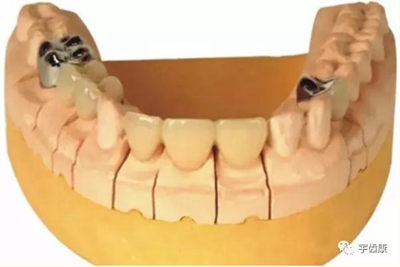

7. 共同就位道的調(diào)節(jié)

8. 實際備牙產(chǎn)生的問題